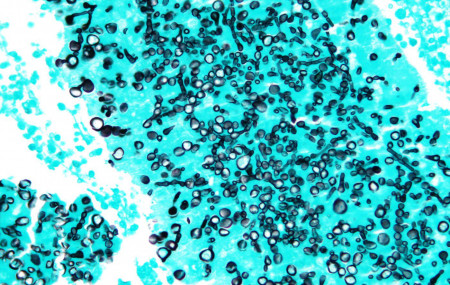

Valley fever is commonly found in soil. (Nephron, Wikimedia Commons) Society

Fungi could be the source of next pandemic

Oladele A. Ogunseitan 2022-07-08 06:37:00